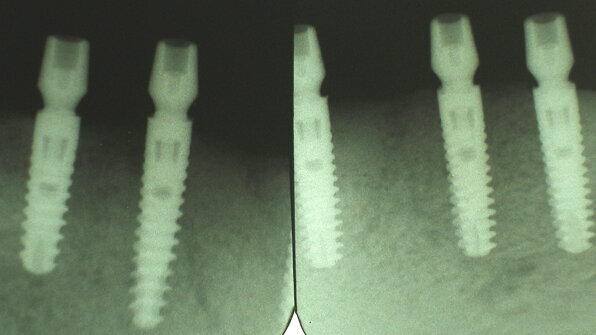

The optimal configuration is four implants placed from mental foreman to foremen (Fig. 8). Four 3.5 mm diameter by 11 mm high are a minimum requirement for the SynCone technique. If 14 mm implants are possible, this is ideal, as most of the early fixation is mechanical in nature. A longer and/or wider implant will provide more primary stability reducing any chance of excessive micro-movement at the bone implant interface as secondary biologic fixation occurs.

The unique surgical protocol is to place the Ankylos implant 1 to 2 mm below the crest of bone1,2 (Fig. 9). The unique sub-crestal positioning is possible as a result of horizontal and vertical room created by the medialized implant abutment connection. This offset creates the necessary room for the soft tissue to reattach. Thus, there is a supra-crestal biologic width, without the accommodative bone loss seen in many conventional implant designs8–17,19 (Figs. 10 & 10a). In addition, the close tolerance of the abutment implant connection creates an invisible micro gap1–19 (Fig. 10b).

The simple surgical technique for a 3.5 mm implant includes the 1.8 mm twist, 2.8 twist, conical reamer and tap-in type 1 and 2 bone. Placement of the first implant is suggested 5 mm anterior to the identified mental foreman bilaterally (Fig. 11a). Then the anterior two implants should be placed with even distribution (Fig. 11b). The SynCone abutment is placed and then long paralleling pins are placed on the abutments. These pins aid in keeping the implant within five degrees of each other, a prerequisite for SynCone success (Fig. 12).